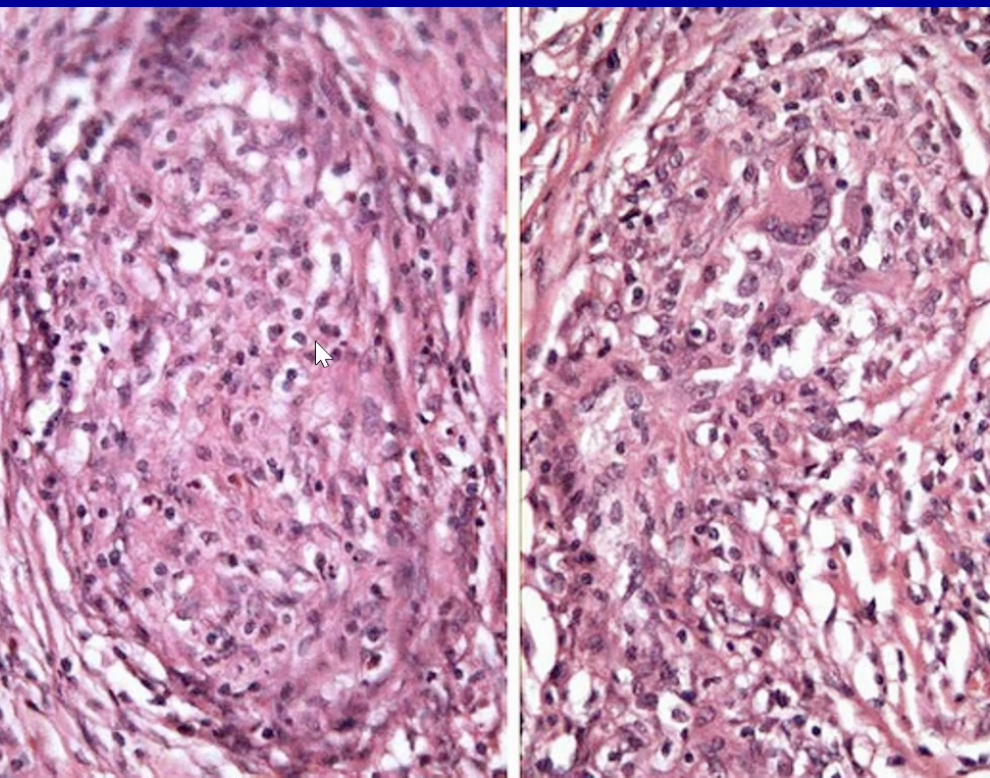

Schiller-Duval Body Yolk Sac

Hyaline globules of yolk sac tumor